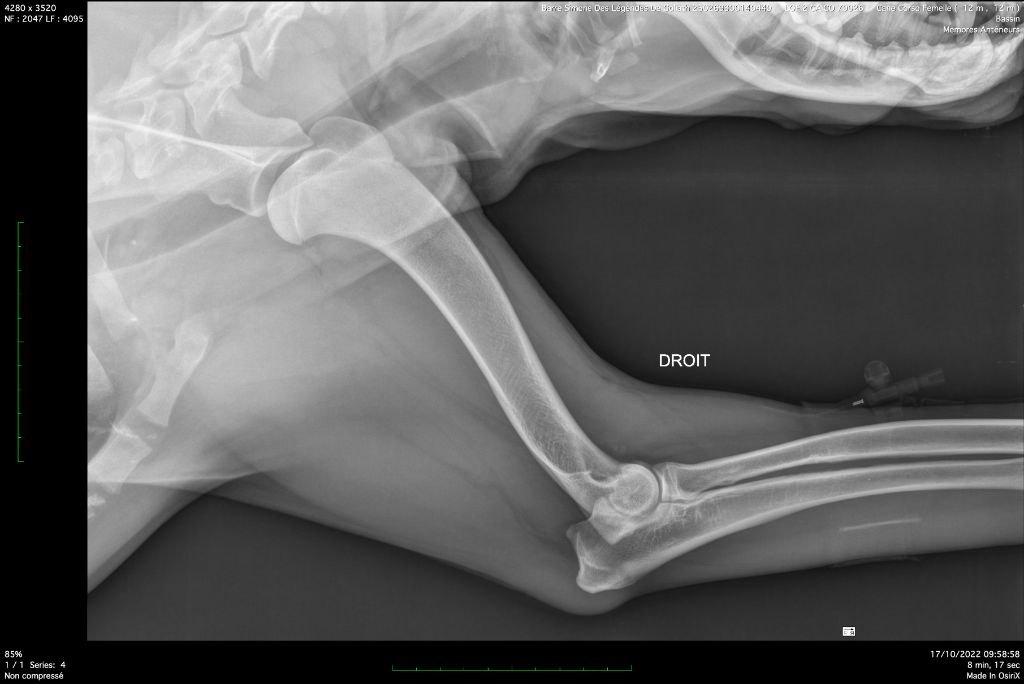

| Couleur | GRIS BRINGE DRSA N/N HD A / ED 0 officiel |